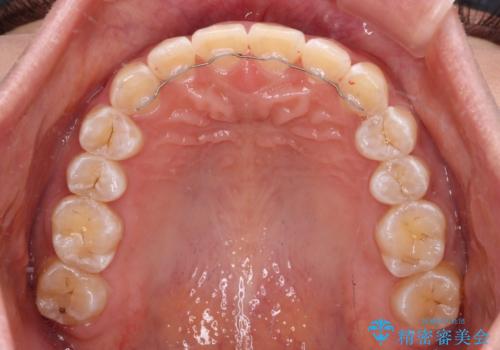

前歯の隙間と上下正中のズレを解消

正中がなかなか合わずに、2年近くの治療期間を要しました。

- 矯正治療後の保定が不十分だと後戻り(元の位置に戻ろうとする動き)をします